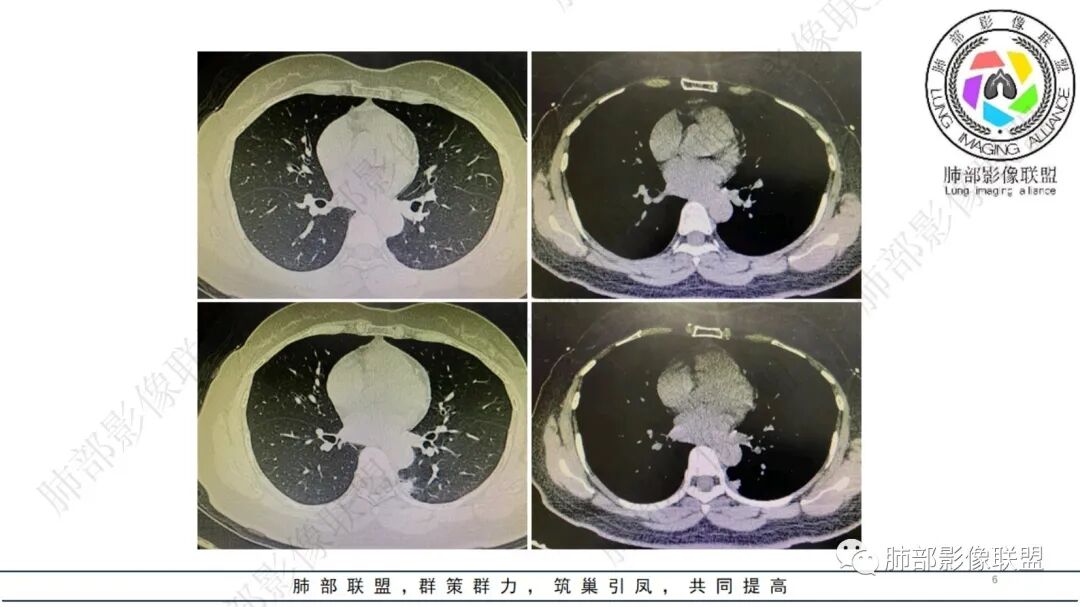

1、右肺上叶混合密度磨玻璃结节特征性较强,尤其是后段病灶,边界清楚,应高度警惕微浸润腺癌,这个不用纠结,我们可以等,定期复查行之有效。

2、临床实践中,左下叶背段类似阴影并不少见,支气管肺组织猬集纵隔旁,常为含气不良,或伴慢性炎症,长期存在。

结合本病例:年轻女性患者,体检发现病灶。影像学表现为左下肺类囊腔样结节,整体边界清楚,实性区域边缘平直、凹陷,缺乏典型分叶毛刺、胸膜改变等,病灶也未显示清楚的磨玻璃勾边,病灶不大而肺门纵隔未见肿大淋巴结,综合考虑慢性炎性肉芽肿可能性较大。必要时可结合病理检查。

肺隔离症也偏内侧,常表现为混杂密度,含液囊性病灶为主。须查实体循环供血证据。